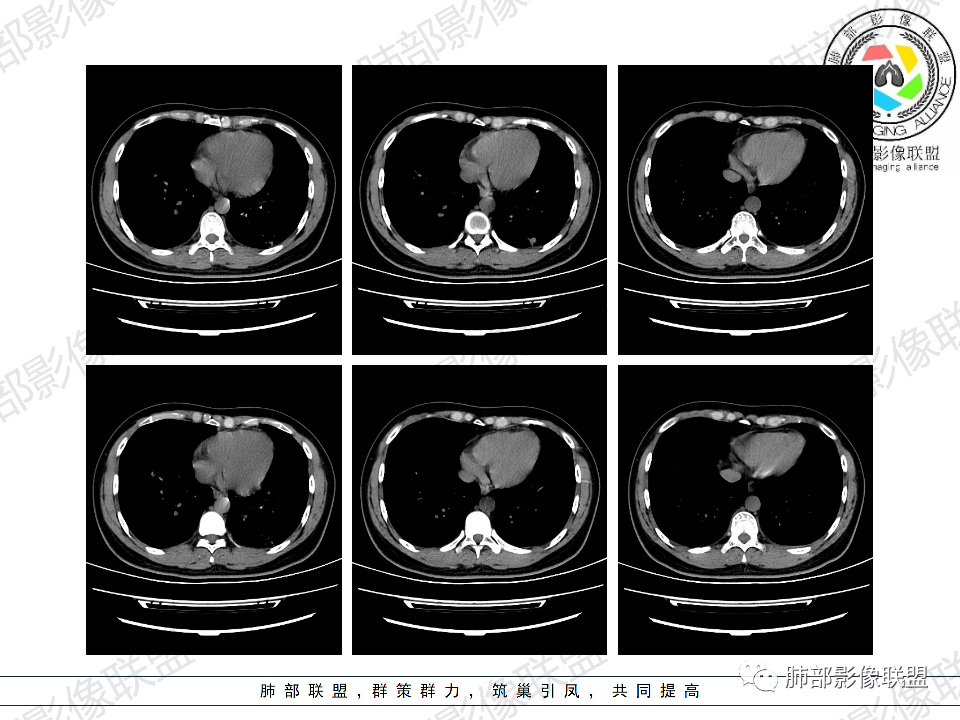

这样的Cd4如此低,病情那么久了,隐球菌的话,脑子应该出问题了,但是患者没有中枢神经系统受损表现,马尼入血后可以出现呼吸困难。诊断真菌性机会性感染没问题,还是马尼>隐球菌。

青年男性,HIV阳性,白细胞及淋巴细胞显著降低,CRP增高,胸闷气喘一周,影像为双肺胸膜下平行于胸膜分布的多发大小不等结节伴晕,单从影像上看,隐球是要首先考虑,但是不好解释临床症状。需要鉴别:1、曲霉所致IPA,临床有粒缺基础,胸闷一周要考虑,但影像不是典型的血道或气道分布又存疑,2、马尼,CD4低,HIV基础,要考虑,但是否有旅广史?另外纵隔淋巴结无肿大,肝脾不肿大,可能稍小。3、PCP,HIV基础,CD4低,胸闷气喘要考虑,影像分布不典型。4、腺病毒或EB病毒感染,HIV基础,影像改变要考虑,但是发病无发热,存疑。5、结核,临床与影像均不典型。可能小。综上,隐球>曲霉>PCP>马尼>病毒感染。下一步,查隐球荚膜抗原,NGS找病原体。

早上有老师提到,说肺里这么多病灶,又是HIV免疫缺陷,一般会合并隐脑。但是我暂时还没发现同时合并隐脑的。

老师们最多鉴别的是马尼。马尼主要还是纵隔淋巴结,腹膜后多发淋巴结,肝脾大。我收集的病例还是以淋巴结肿大显著,有的时候双肺可以干净的很,可能就在一个角落里孤立的一个空洞

2、类型:常见有孤立肉芽肿型、肺炎实变型、混合型(多发结节/实变/空洞)、弥漫粟粒/间质型。免疫正常宿主多表现为孤立肉芽肿型,也可以表现为肺炎实变型或混合型。免疫缺陷宿主则容易肺内播散形成多发(结节、实变、空洞)或弥漫粟粒/间质型,可累及中枢系统并发隐球菌脑炎。

4、实验室:血象一般正常,少数可出现白细胞升高;G及GM试验阴性;隐球菌荚膜多糖抗原试验阳性(特异性高,敏感性各异)常提示诊断。